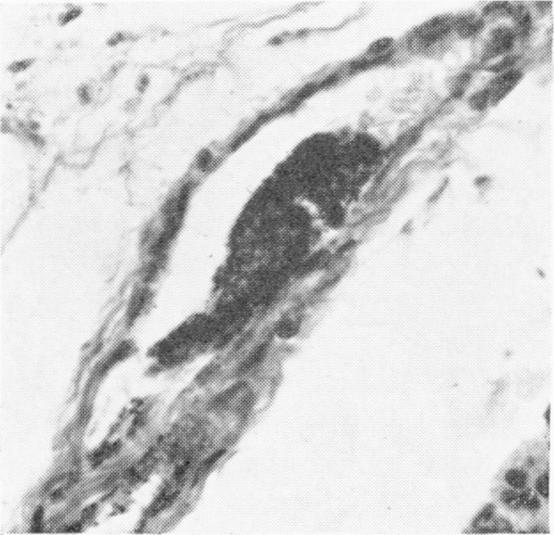

Disseminated fibrin thromboembolism among neonates dying within 48 hours of birth.

Arch Dis Child. 1967 Aug;42(224):401-9. doi: 10.1136/adc.42.224.401.